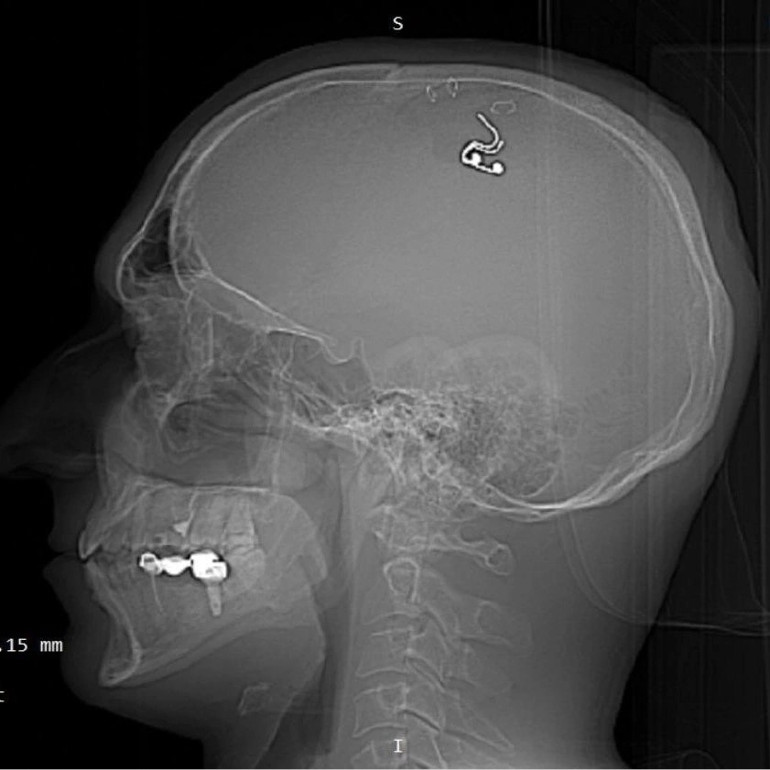

Kaldırıldığı sağlık kurumunda acilen ameliyata alınan Mikhail Raduga’nın kafatasına yerleştirdiği çip çıkarılırken, hayati tehlikeyi atlattığı açıklandı.